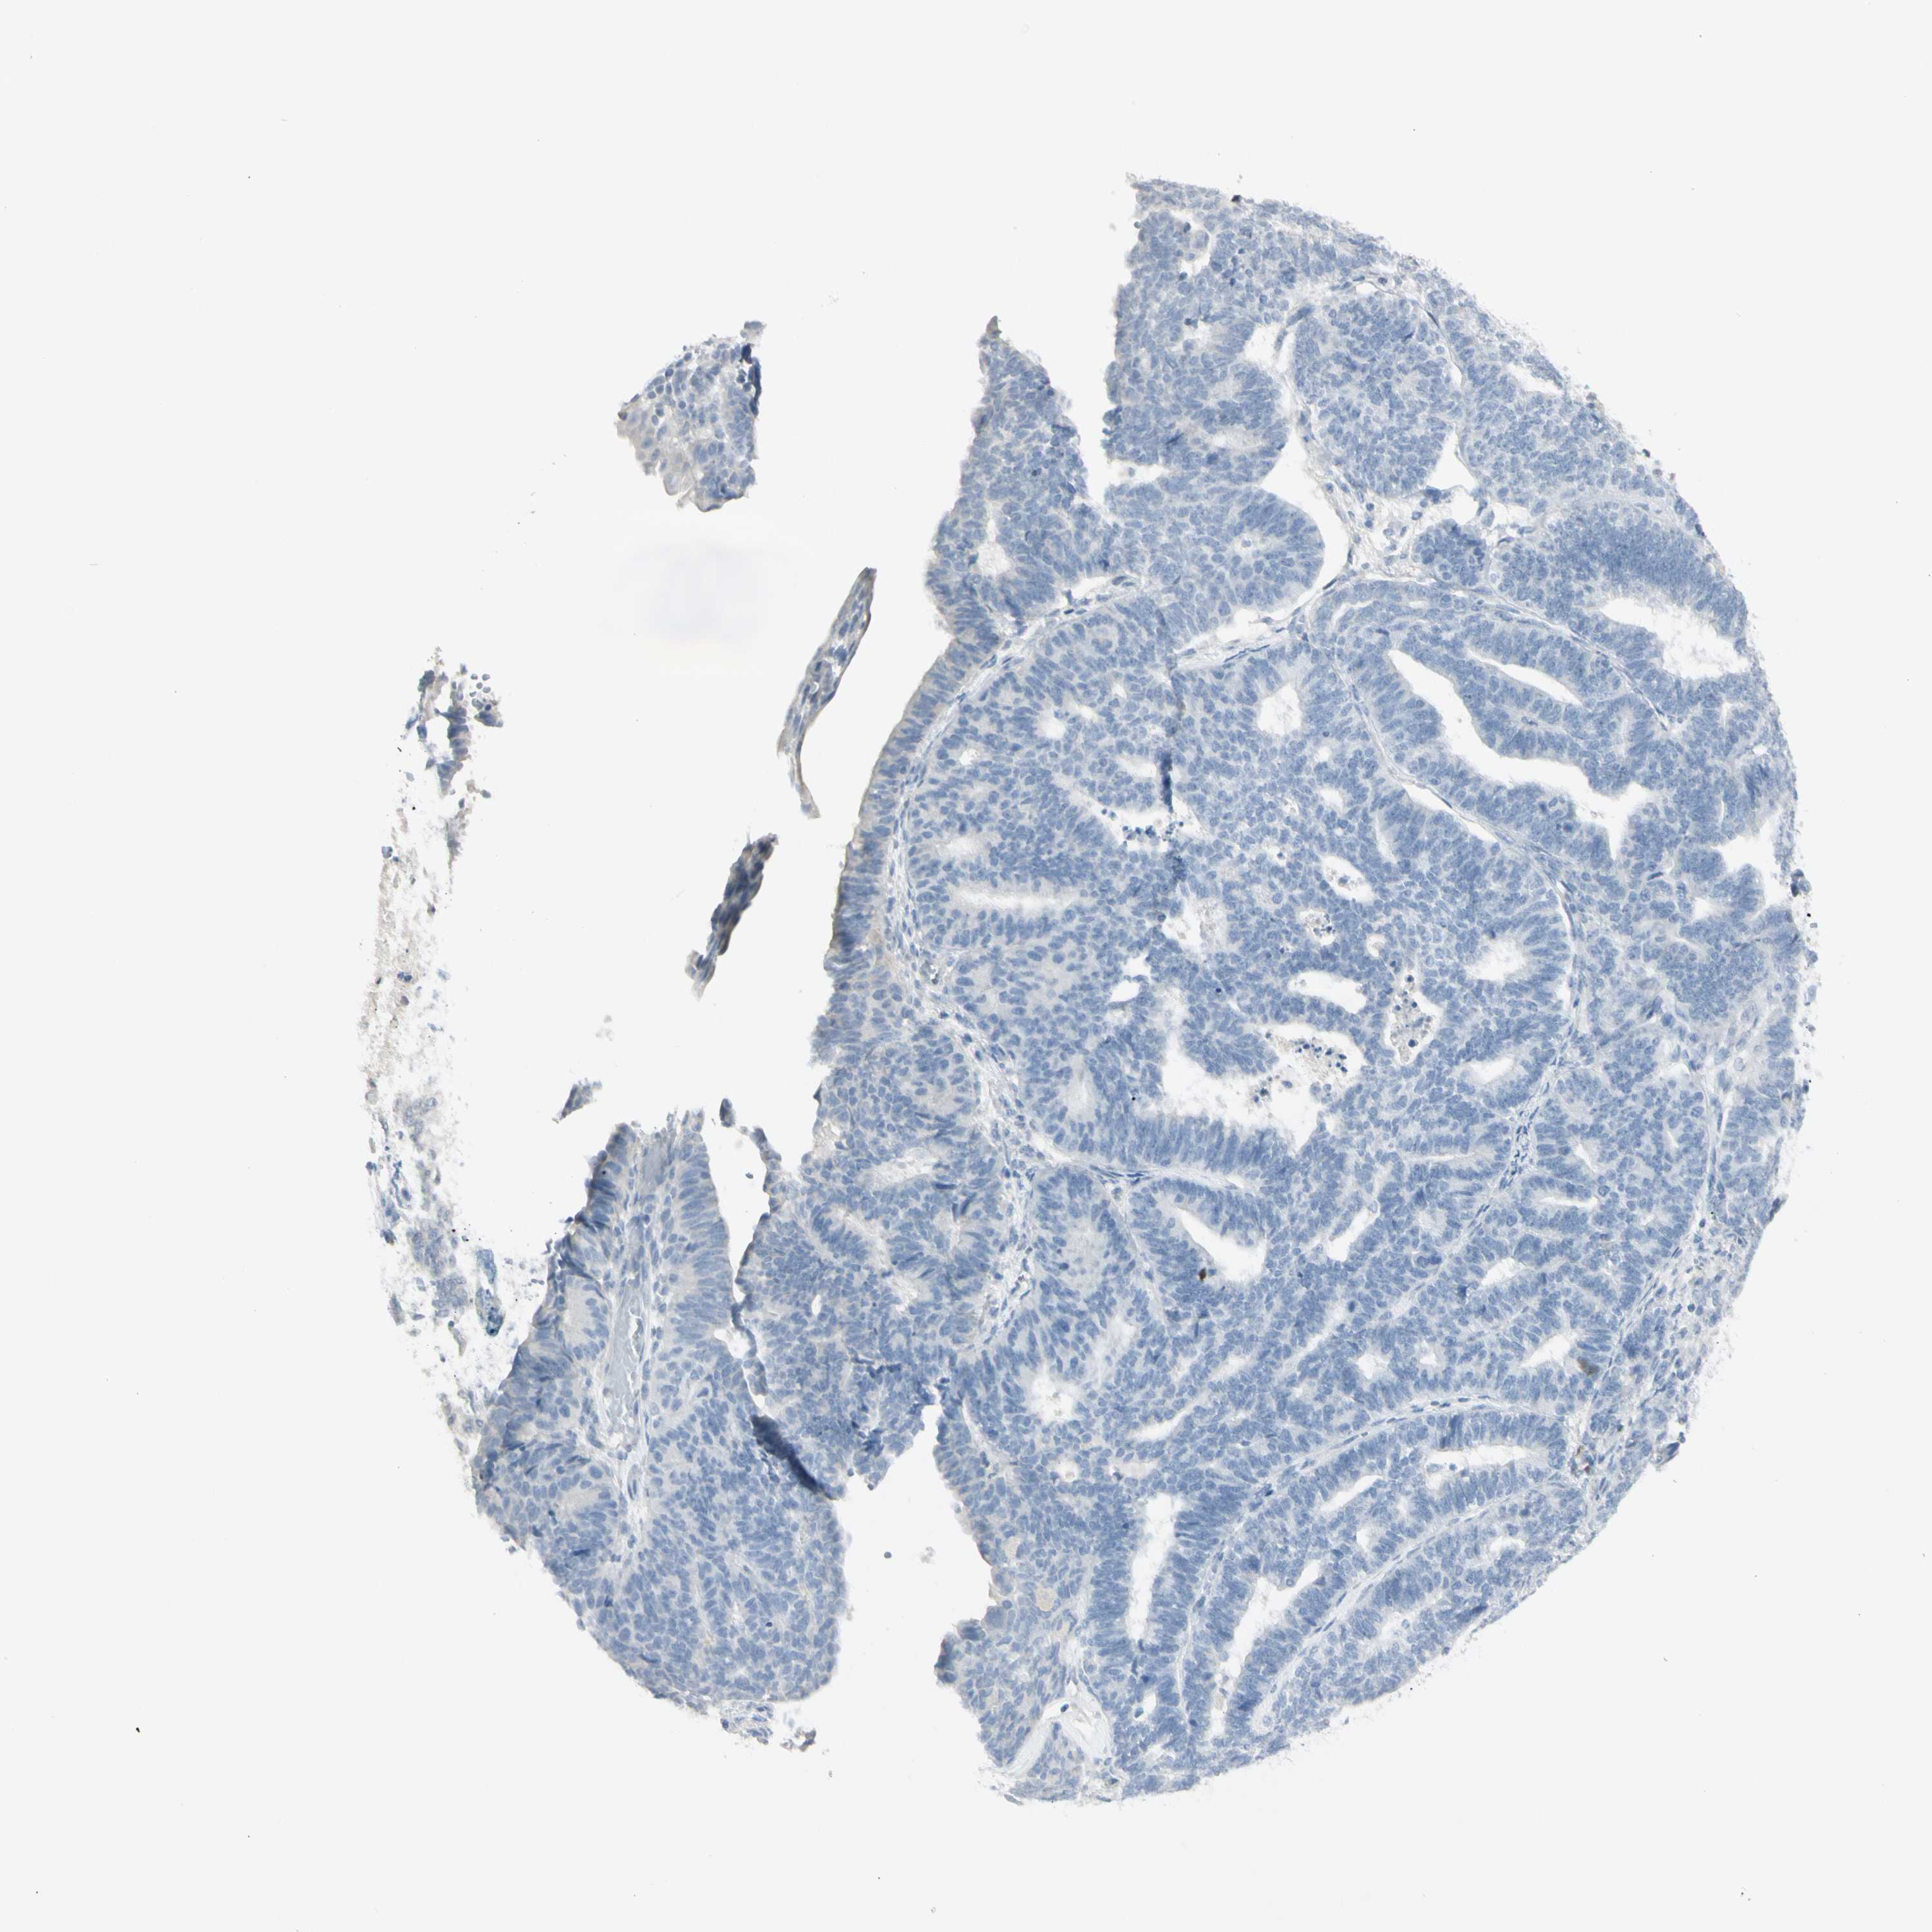

ENDOMETRIAL CANCER - Protein expressioni

A mouse-over function shows sample information and annotation data. Click on an image to view it in a full screen mode. Samples can be filtered based on level of antibody staining by selecting one or several of the following categories: high, medium, low and not detected. The assay and annotation is described here.

Note that samples used for immunohistochemistry by the Human Protein Atlas do not correspond to samples in the TCGA dataset.

Antibody stainingi

Antibody staining in the annotated cell types in the current human tissue is reported as not detected, low, medium, or high, based on conventional immunohistochemistry profiling in selected tissues. This score is based on the combination of the staining intensity and fraction of stained cells.

Each image is clickable and will lead to virtual microscopy that enables deeper exploration of all samples and also displays staining intensity scores, fraction scores and subcellular localization as well as patient and tissue information for each sample.

Antibody HPA009177

Antibody CAB002661

Staining

High

Medium

Low

Not detected

Intensity

Strong

Moderate

Weak

Negative

Quantity

>75%

75%-25%

<25%

None

Location

Nuclear

Cytoplasmic/membranous

Cytoplasmic/membranous,nuclear

Adenocarcinoma, NOS

Neoplasm, malignant, NOS